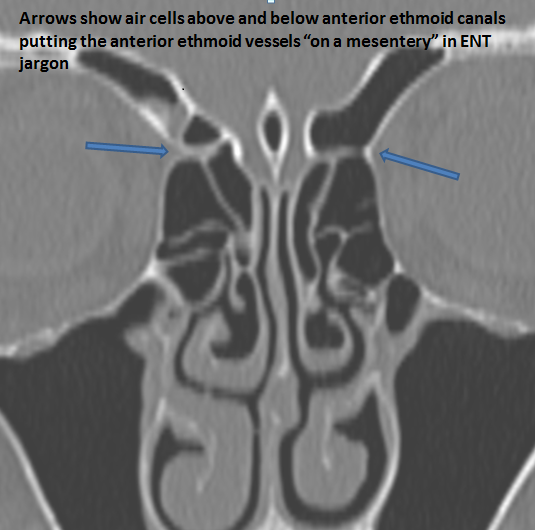

The anterior ethmoid arteries are on a mesentery.